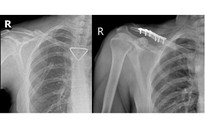

Nói về chuyển đổi số để cải tiến chất lượng, bác sĩ Lời cho biết bệnh viện ứng dụng hệ thống lưu trữ và truyền tải hình ảnh y tế (PACS) trong siêu âm, X-quang, CT giúp tối ưu hóa quy trình làm việc, giảm thời gian chờ đợi cho bệnh nhân, tiết kiệm chi phí in ấn và quản lý hình ảnh hiệu quả hơn.